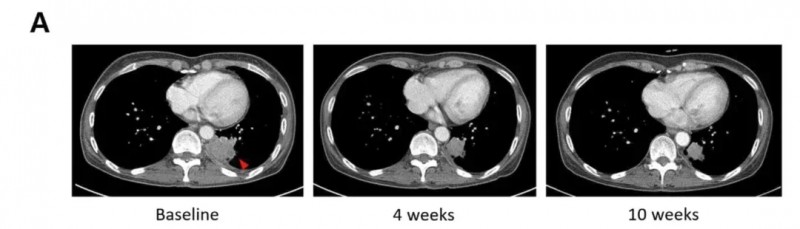

另一例患者,在左上肺叶切除术2年后腺癌复发(活检证实),在先前的吉非替尼和奥西替尼治疗失败后,接受SNKO1联合西妥昔单抗/吉西他滨/卡铂作为三线治疗。影像学检查示,治疗后病灶明显缩小(详见下图)。

▲图源“BMJ”,版权归原作者所有,如无意中侵犯了知识产权,请联系我们删除